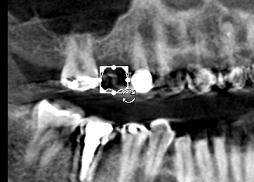

The position of an imported crown can be adjusted manually in the Curve tab, using the object editing tools displayed in the following view screens:

Reconstructed Panoramic View Screen ![]()

Axial Slice View Screen |

Reconstructed Panoramic (Trace) View Screen |

Oblique-Coronal Slice View Screen |